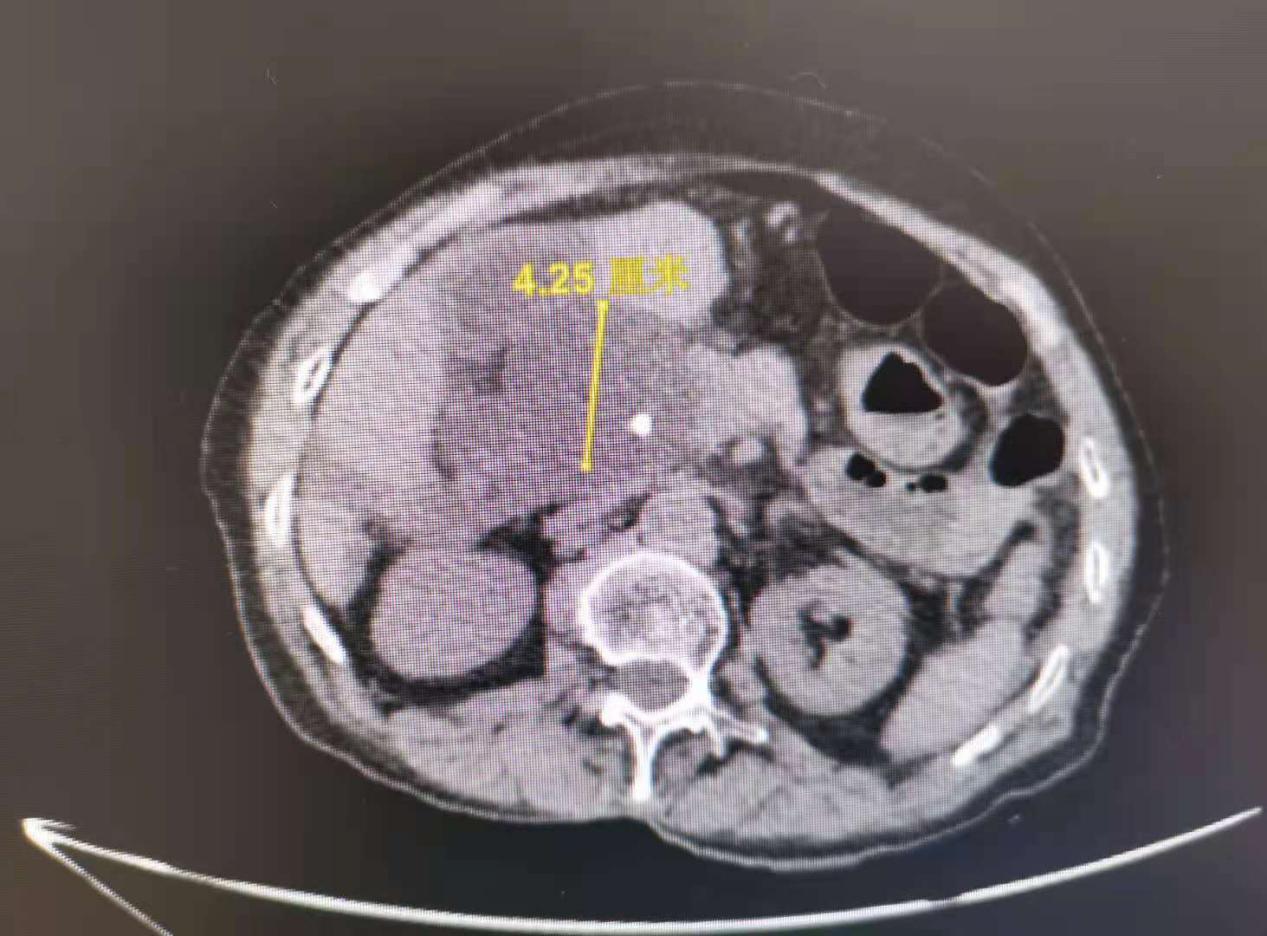

76岁的李奶奶来自江西中部地区某城市,近日无故出现疼痛、腹胀等症状,疼痛难忍的她由其家属带到当地医院就诊。本以为只是普通的消化不良,但行腹部CT及磁共振检查发现胆管结石并胆总管巨大囊肿、胆管内嵌顿一枚(异物)支架,其中1颗结石足有10毫米大,都需尽快取出,否则腹痛会越来越严重。按照传统的治疗,要取出胆总管的石头及嵌顿异物(支架),需做胆管结石开腹手术或腹腔镜下胆管探查取石术,手术时间长,并发症发生率高,住院时间长,治疗费高,李奶奶以及家属一想到这些就退缩了。

胆胰管开口在十二指肠降部,ERCP操作需将十二指肠镜从口腔插入患者体内,经食管、胃部至十二指肠降部、经十二指肠乳头注入造影剂,由于镜身盘绕及视线局限,很难前进,可谓每一毫米都需要调整定位,非常考验操作者的技术。经过反复探查找到李奶奶的嵌顿于胆总管内的(异物)塑料支架,章诺贝教授迅速插入取石网篮将其安全取出,同时见数枚大小不等的结石随之掉入十二指肠腔内,而结石最大者足有10毫米。术中并留置5根塑料支架于肝总管,为避免支架滑脱置入一枚和谐夹于乳头表面进行塑形,最后置入一根鼻胆道引流管于左肝管,胆汁引流通畅,全操作过程一气呵成,耗时五十分钟!